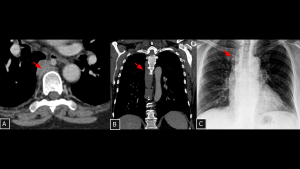

Fig 12: Case 13 – Ectopic parathyroid gland:

Panels A, B, and C demonstrate an elongated, well-defined solid nodule posterior to the esophageal wall (visceral mediastinum) (arrows in A and B), with apparent arterial supply originating near the thyroid gland. This lesion was identified as a hyperfunctioning ectopic parathyroid gland on technetium-99m sestamibi scintigraphy (C).

SYSTEMATIC APPROACH: 1. Age: Adults. | 2. Morphology: Oval nodule. | 3. Enhancement: Avid enhancement (Wash-in/Wash-out). | 4. Relevant Anatomical Relationships: Visceral compartment (along the migration pathway of the glands).